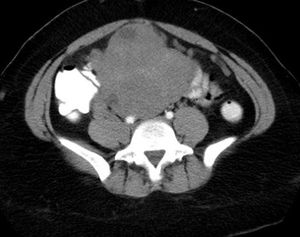

Incarcerated hernia: X-ray and CT scans evaluate inquinal swelling and and long-term swelling in elderly males.